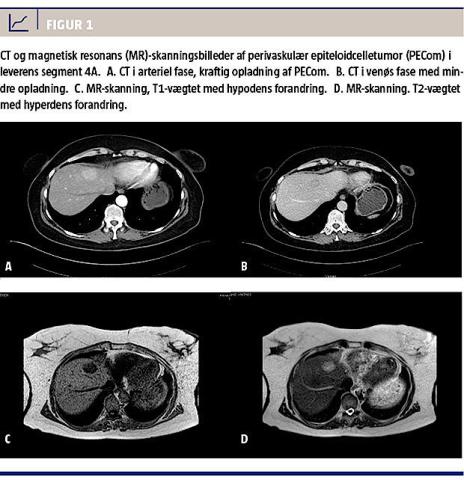

På den præoperative CT af abdomen fandt man en 3 × 2 cm hypovaskulær proces i leveren med kraftig opladning i den arterielle fase og mindre opladning i den venøse fase. En magnetisk resonans-skanning viste en hyperdens forandring ved T2-vægtning (Figur 1D). Initialt havde man mistanke om fokal nodulær hyperplasi eller levermetastase. Ved kontrastforstærket laparoskopisk ultralydundersøgelse fandtes en solitær hypodens proces med kraftigere udvaskning af kontraststoffet i senfasen, hvilket var foreneligt med metastase. Tumoren blev reseceret i samme seance.

Billeddiagnostisk er der ingen sikre kriterier til differentiering af PECom i forhold til andre levertumorer, men grundlæggende er det velvaskulariserede tumorer med tidlig og kraftig kontrastopladning i den arterielle fase og mindre i den venøse fase [5].